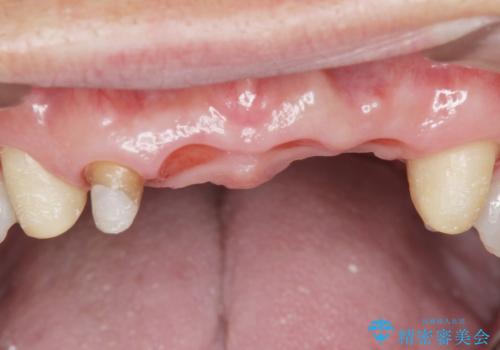

- お風呂場で転んで上の前歯が2本抜けてしまったことを主訴に来院された患者様です。

精査したところ、左上の側切歯(左上2)も破折しており保存不可能な状態でした。

左上の側切歯(左上2)を抜去し、右上の側切歯(右上2)の再根管治療後、セラミックのブリッジによる補綴を行いました。